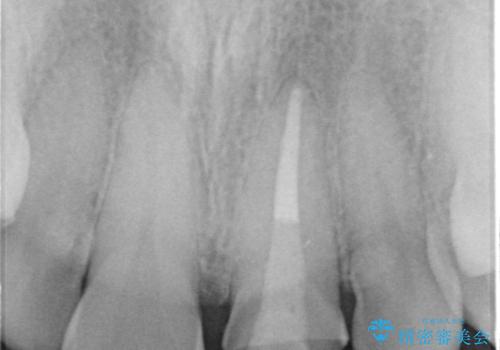

根管治療からのやり直しをした後、ジルコニアクラウンで色調の改善をしていきます。

被せ物を装着する際は、歯の中(根管)から綺麗にすることも重要となります。